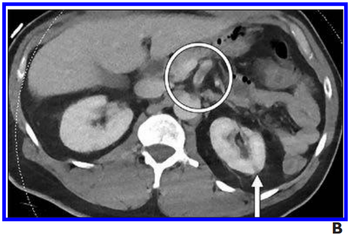

Thromboembolic findings in the abdomen and pelvis appear more often in patients with viral infection.

Findings captured during emergency scans intended to pinpoint stroke can reveal viral infection.

Nearly 20 percent of patients infected with the virus show up with gastrointestinal – but no respiratory – complaints.